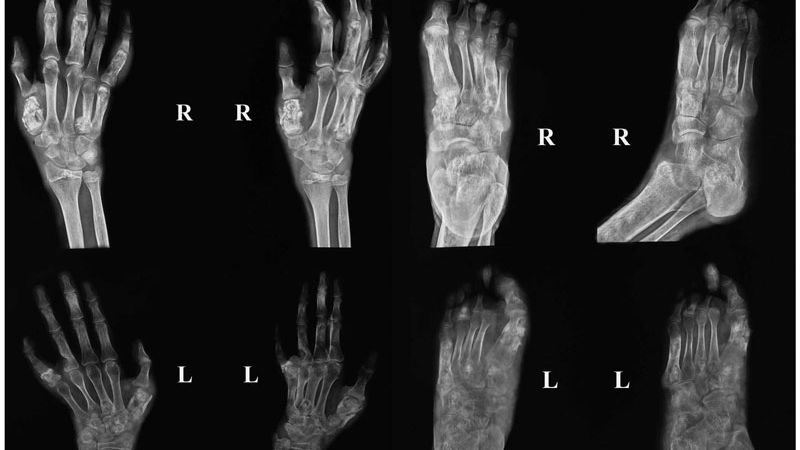

Vi khuẩn này có thể lây lan qua đường máu từ phổi hoặc các cơ quan khác đến xương và gây tổn thương ở một hoặc nhiều vị trí. Các vị trí thường bị ảnh hưởng nhất là cột sống, xương cổ, xương chậu, xương ức, xương sườn, xương bàn tay và bàn chân.[1]

Chụp X-quang, CT hoặc cộng hưởng từ MRI: Nếu bạn có các triệu chứng như biến dạng xương, bác sĩ có thể yêu cầu thực hiện X-quang, CT scan hoặc MRI để đánh giá mức độ tổn thương.[3]

Các biện pháp chẩn đoán hình ảnh giúp quan sát và đánh giá được tình trạng của xương